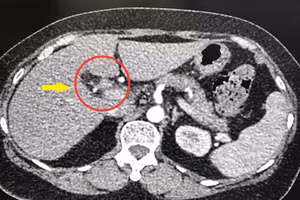

GD&TĐ - Khoa Viêm gan, Bệnh viện Bệnh Nhiệt đới Trung ương tiếp nhận bệnh nhân vàng da nặng và suy gan cấp do tự ý ngừng thuốc điều trị viêm gan B.